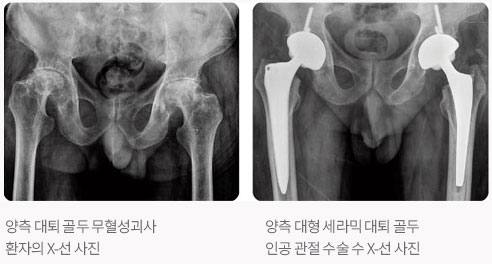

본원에서는 최신의 수술 기법과 인공 관절 기구(최소 절개 수술법, 대형 세라믹 대퇴 골두 치환술, 고도굴곡형 인공 슬관절 치환술)를 사용하여 연간 200명 이상의 환자들에게 통증없는 생활로의 전환을 도와드리고 있습니다.

우측 퇴행성 고관절염 및 좌측 선청성 고관절 변형

- 32mm 대형 세라믹 골두 인공 고관절 전치환술 및 자가골 이식술 시행

수술 후 경과는 대개 수술 후 2주 이내에 목발 보행이 가능하고 수술 후 3개월 까지는 목발의 사용이 필요합니다. 그러나 심한 기형으로 근육 연장술, 골단축술 등을 시행한 경우에는 골유합 기간과 근력회복 등의 치료때문에 경과가 늦어지게 됩니다. 그리고 수술 후 약 3~6개월 정도 지나면 정상에 가까운 보행이 가능합니다. 수술 후에 단기적으로 생길 수 있는 합병증으로는 감염, 혈전증, 탈구 등이 있을 수 있습니다. 수술 후 회복이 되고 충분한 기간이 지난 후에 장기적으로 생길 수 있는 합병증으로는 인공 관절의 해리, 즉 인공 관절이 뼈에서 고정이 이완되고 마모되는 현상입니다. 삽입된 인공 관절을 사용할 수 있는 기간은 평균 10~15년 정도 입니다. 대개 15년 사용후에 20% 정도에서는 재치환술의 대상이 되고 있습니다. 젊은 사람 일수록 활동량이 많고, 오랜 기간 동안 관절을 사용하여야 하기 때문에 인공 관절의 수명은 짧을 가능성이 많아서 마모가 적고 마찰개수가 적은 제품(세라믹 인공 관절)을 사용하여야 재수술의 빈도를 줄일수가 있습니다. 그러나 인공 고관절의 수명이란 꼭 10년 또는 15년이라고 단정 지을 수 없고 쓰는 사람이 얼마나 무리가 가는 행동을 하지 않고 조심스럽게 사용하느냐에 따라서 더 연장될 수도, 더 단축될 수도 있으리라 생각됩니다.

인공 관절의 수명을 좌우하는 부분을 주로 관절을 이루는 삽입물의 재질로써, 초창기부터 최근까지 사용되온 폴리에틸렌이란 플라스틱 종류의 고분자 물질은 과다 사용시 마모가 빠른 문제로 10년 정도 지나면 인공 관절을 바꿔줘야하는 문제가 있었습니다. 그러나 최근 10년전부터 마모가 거의 없이 반영구적으로 사용할 수 있는 세라믹 재질의 인공 관절이 개발되어 널리 사용되면서 이러한 문제가 해결되어가고 있어 조심해서 사용시 20년 이상의 수명을 예상하고 있습니다.